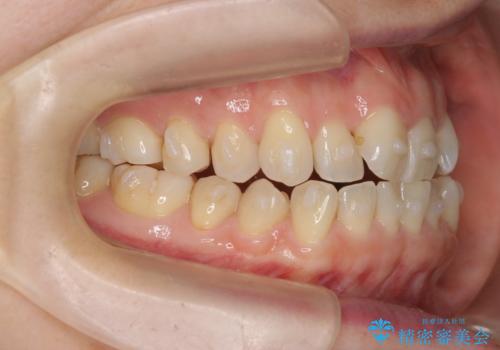

前歯の目立つガタつきをマウスピース矯正で治療

- 大きく傾いてしまった前歯のガタつきの改善を求めて来院されました。

前歯のガタつきをしっかりと取り、機能的・審美的に理想的な歯並びをマウスピース矯正で達成します。

強度のガタつきはマウスピース単体では並び切ることが難しいこともありますが、しっかりと装着していただいたことで良好な治療結果を得ることができました。